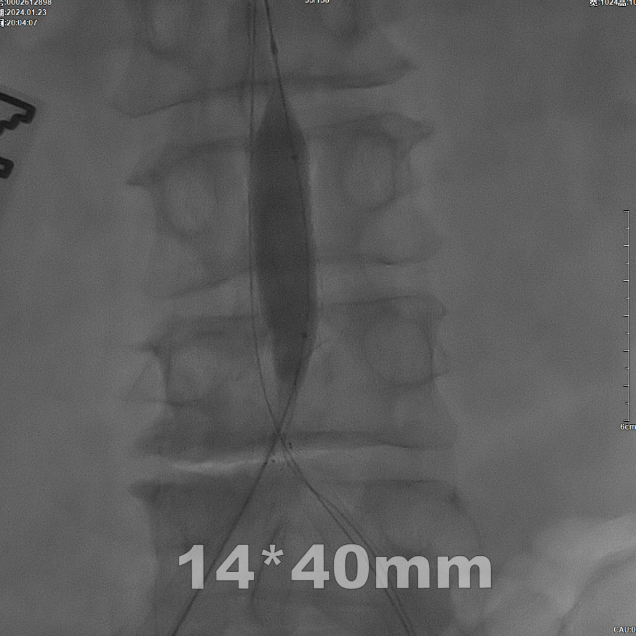

后扩张处理

首先使用14mm球囊进行初步扩张,鉴于腹主动脉直径约15mm,最终选用16mm球囊进行扩张。

CERAB技术关键点二:先用14mm×40mm球囊分别扩张双侧髂肢的腹主动脉段。